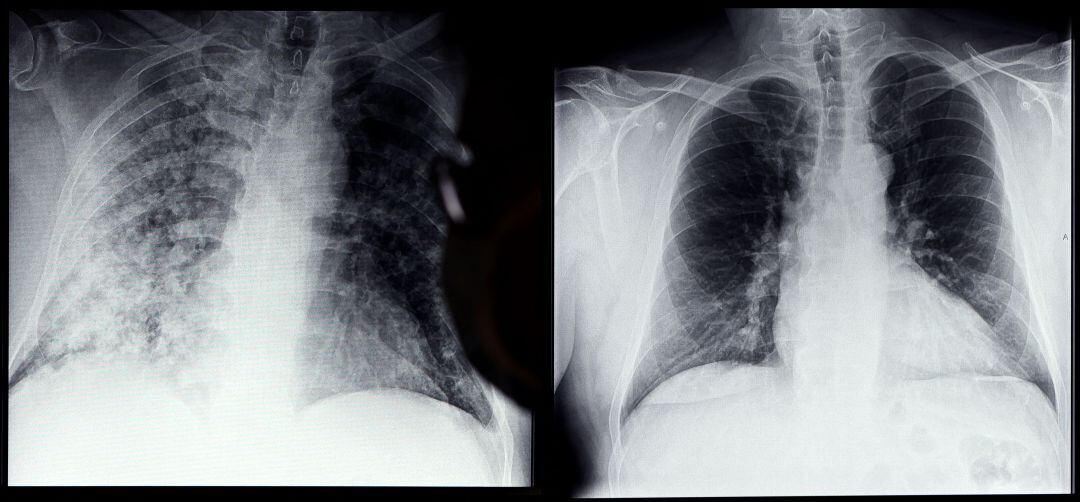

Este sistema informático es capaz de analizar miles radiografías que muestran el estado de los pulmones de personas. / GETTY IMAGES

Un nuevo sistema de inteligencia artificial anticipa qué pacientes de COVID pueden sufrir complicaciones mortales. Este sistema informático es capaz de analizar miles radiografías que muestran el estado de los pulmones de personas que han sido contagiadas por el SARS COV-2 y ya ha sido probado, con éxito, en más de 700 pacientes, que sufrían casos graves de la COVID- 19.

En concreto, desarrollado por investigadores de la Facultad de Medicina Grossman de la Universidad de Nueva York, este programa utiliza varios cientos de gigabytes de datos extraídos de 5.224 radiografías de tórax tomadas de 2.943 pacientes gravemente enfermos infectados con SARS-CoV-2, el coronavirus que provoca la Covid 19.